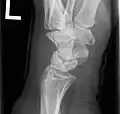

X-ray showing stage IIIB on right wrist, with ulnar impingement.